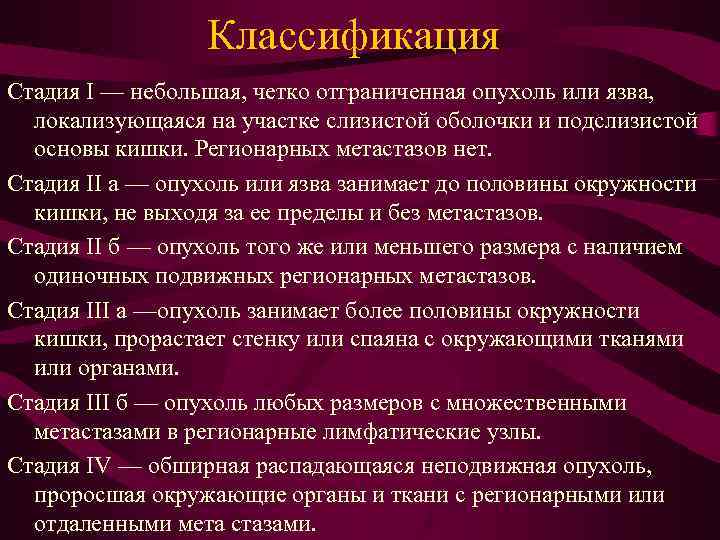

Классификация Стадия I — небольшая, четко отграниченная опухоль или язва, локализующаяся на участке слизистой оболочки и подслизистой основы кишки. Регионарных метастазов нет. Стадия II а — опухоль или язва занимает до половины окружности кишки, не выходя за ее пределы и без метастазов. Стадия II б — опухоль того же или меньшего размера с наличием одиночных подвижных регионарных метастазов. Стадия III a —опухоль занимает более половины окружности кишки, прорастает стенку или спаяна с окружающими тканями или органами. Стадия III б — опухоль любых размеров с множественными метастазами в регионарные лимфатические узлы. Стадия IV — обширная распадающаяся неподвижная опухоль, проросшая окружающие органы и ткани с регионарными или отдаленными мета стазами.